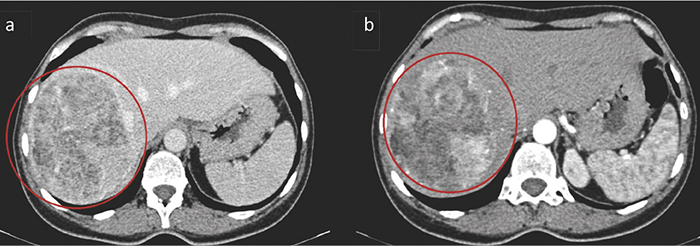

An abdominal computed tomography (CT) scan of the liver, diaphragmatic surface, subcapsularly in segments VII/VIII/V/VI, showed a large tumour up to 13×10×13 cm with fatty inclusions, hypervascularised internal structures and calcinates (Figure 1). Tumour was fed by hypertrophied branches of the right hepatic artery. The convex surface of the mass is in contact with the intrahepatic part of the inferior vena cava in the upper part, and is deformed by the branches of the right hepatic vein slightly below. The trunk of the portal vein and the right branch are intact. In segment VI, several low-density foci of up to 8 mm are visible. Intrahepatic bile ducts and common bile-prominent in the peripheral parts, nevertheless not dilated.

figure-1414.jpg

Figure 1. Hepatic angiomyolipoma in the right lobe of the liver (marked with red circle). A well-differentiated, circumscribed formation with uneven density due to fat and a denser soft tissue component (a). In the arterial phase, the part of the tumour without fat accumulates contrast (b)